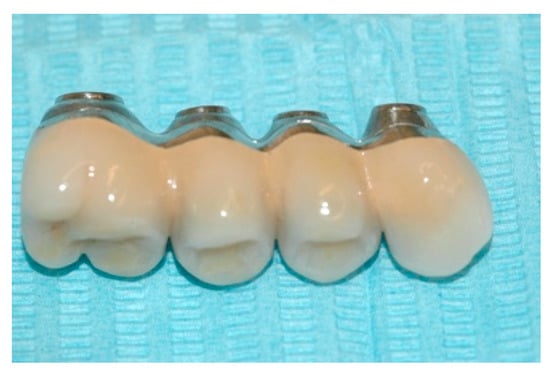

Upon positive feedback, the construction of a superstructure was carried out by performing fusion and subsequent ceramicization in the laboratory (Figure 10 and Figure 11).

Figure 10. The built superstructure.

Prosthesis 02 00023 g010

Figure 11. The built superstructure.